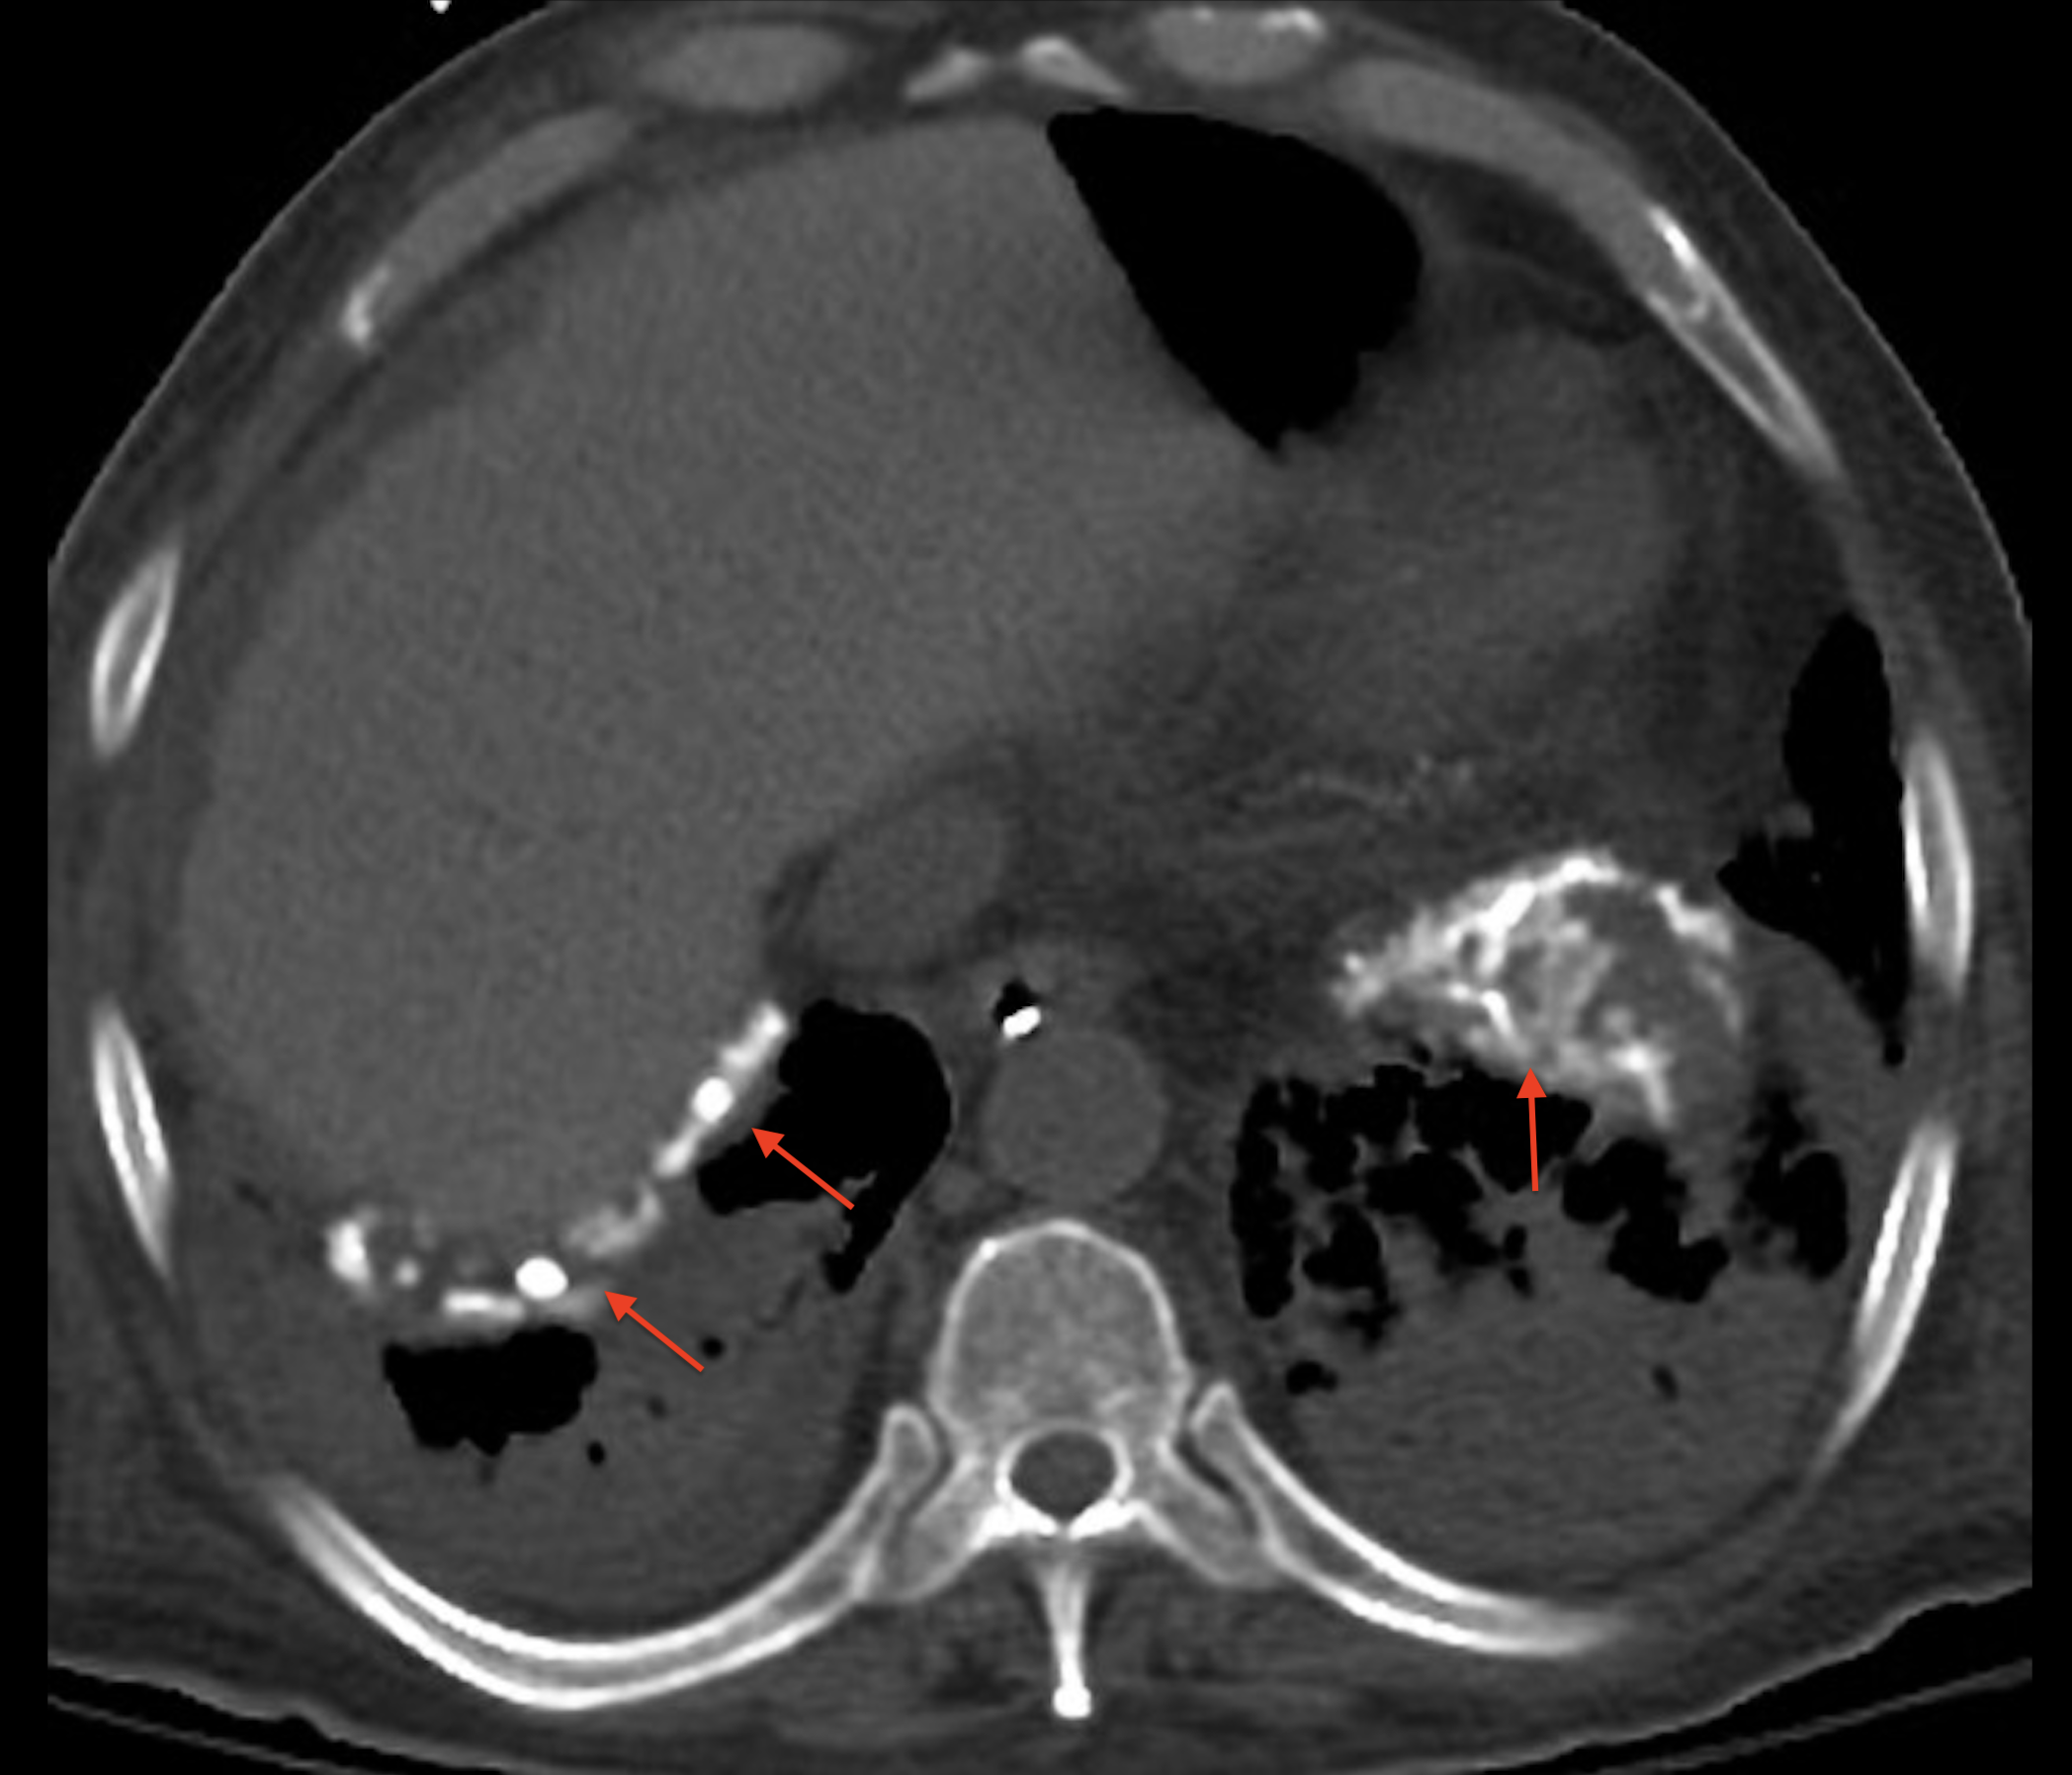

On reconnaît les plaques pleurales facilement lorsqu’elles sont multiples, volumineuse et calcifiée. À un stade précoce il faut attentivement analyser les contours de la plèvre périphérique, coupe par coupes dans les deux fenêtres parenchymateuses et médiastinales pour repérer un épaississement très modérée (quelques millimètres), visible sur parfois moins de 1 cm.

• Radiographie conventionnelle : les plaques pleurales apparaissent comme des opacités bien délimitées, souvent bilatérales et symétriques. Elles se présentent sous la forme de bandes linéaires ou denses le long de la paroi thoracique, en particulier au niveau des régions costophreniques et des sillons interlobaires. La présence de calcifications dans les plaques peut également être observée.

• Tomodensitométrie (scanner) : c’est l’examen le plus sensible pour détecter les plaques pleurales. Il permet une évaluation détaillée de leur taille, de leur distribution et de leur caractère calcifié. Les plaques apparaissent comme des épaississements de la plèvre avec une densité tissulaire, et peuvent être mieux visualisées grâce à la reconstruction multiplanaire.